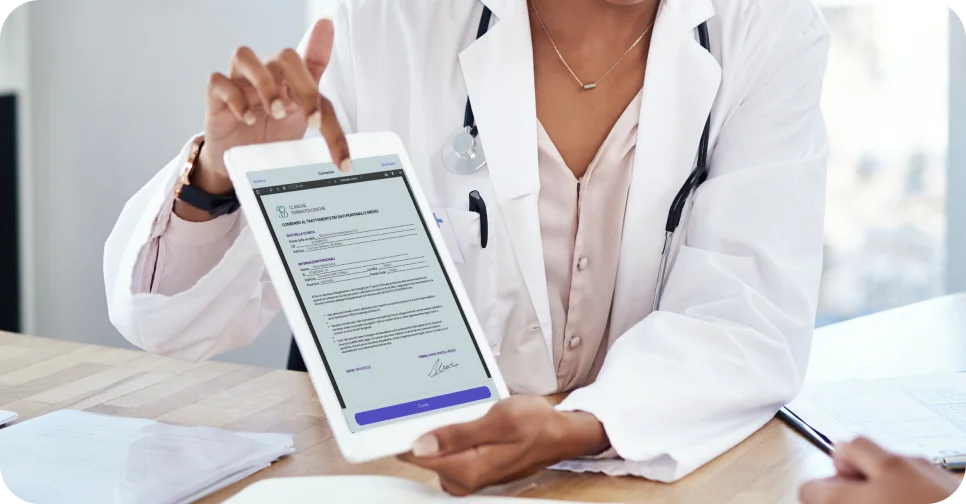

Garantisci una gestione efficace e affidabile della tua clinica, garantendo la firma digitale dei consensi medici e rispettando la normativa GDPR.

Archivia in modo sicuro la documentazione medica del paziente e monitora la tracciabilità dei materiali di consumo per preservare la sicurezza del paziente.